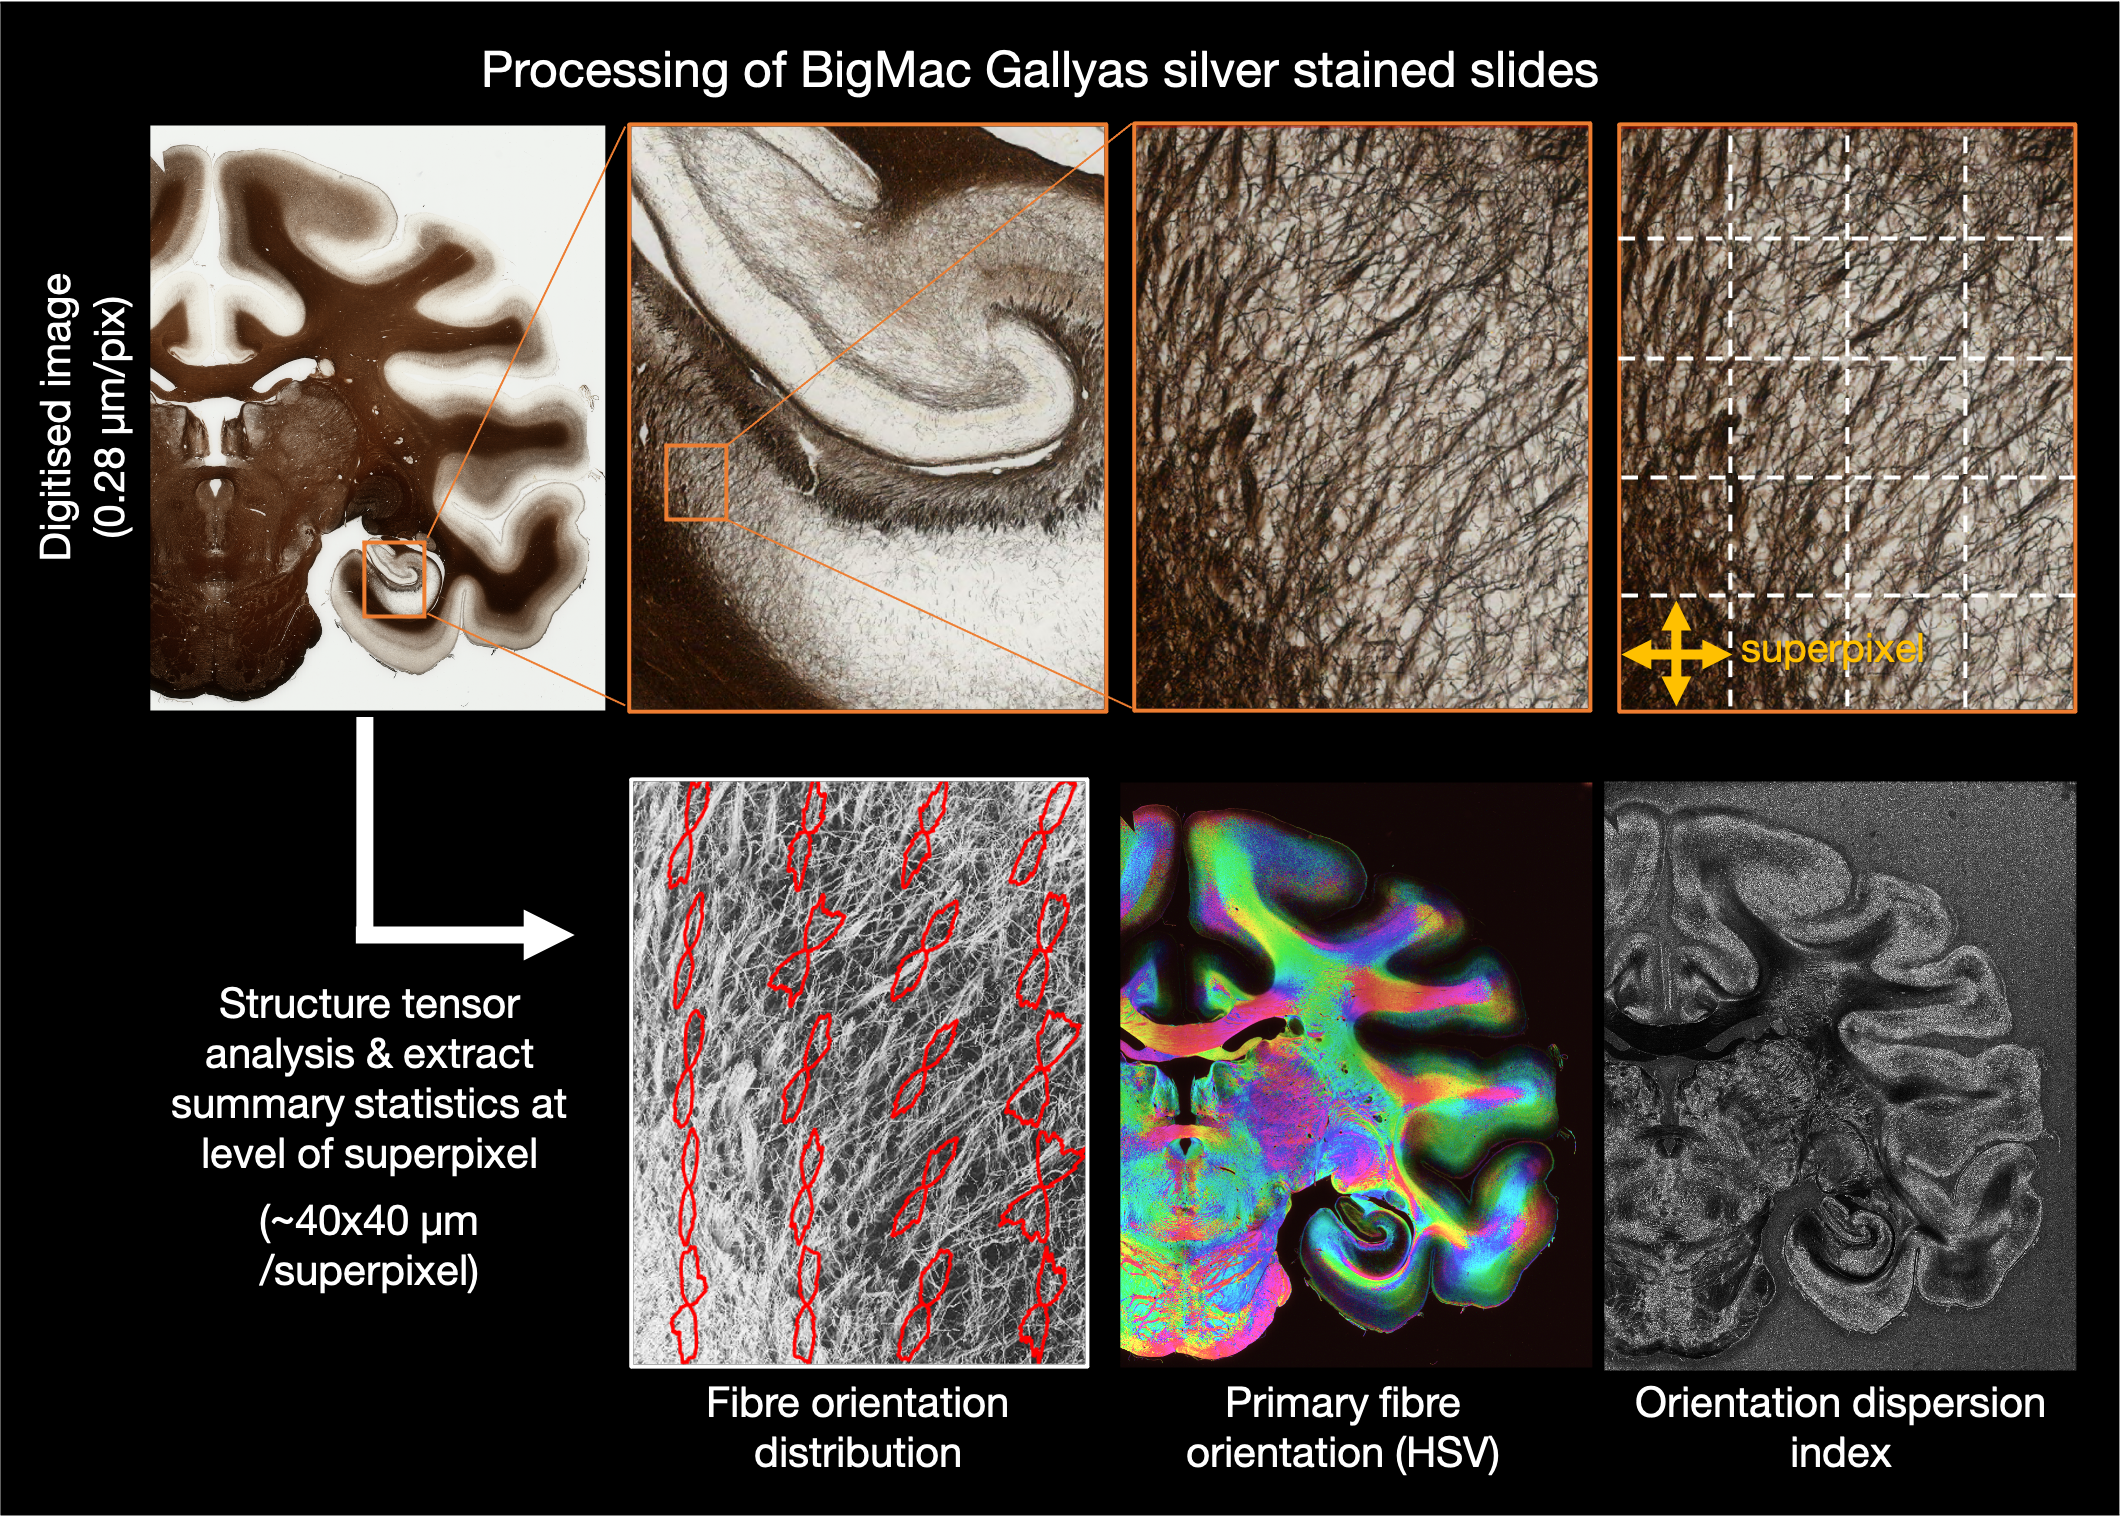

Myelin-stained histology

A different set of tissue sections (also 50 μm thick) were stained using Gallyas silver to visualise myelin. The Gallyas silver stains myelin brown, where the sections were then digitised using an Aperio slide scanner with a 20x/0.75 NA objective lens and a 2x magnification lens, to give a resolution of 0.28 μm/pixel. Due to the large slide size, many of the central sections were digitised in two images (labelled image ‘a’ and ‘b’).

Structure tensor analysis

The digitised images were subsequently processed using structure tensor analysis (Bigun2005, Budde2012) to estimate the primary fibre orientation per pixel. Here we use a Gaussian kernel of 10 μm and estimate summary metrics over a local neighbourhood (superpixel) of 150x150 pixels, which is approx 40x40 μm. The summary metrics include:

HSV - the colour coded mean orientation weighted by the staining density

Orientation - the mean in-plane fibre orientation across the superpixel

RBG thumb - mean RGB value for superpixel

FOD - the fibre orientation distribution - a frequency histogram of all fibre orientations within the super pixel.